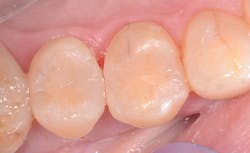

Okay, you're probably wondering, "If it cures so quickly, am I going to have to rush to get it done?" Not so. The special light filter means ambient light will not prematurely set the material. Also, the material is easy to adapt to the preparation, so placement time is reduced in trying to shape the anatomy. The ease of sculpting means less time refining anatomy and polishing, which again shaves off those precious seconds that add up to a big time savings.

Another property to look for in your bulk fill is whether or not it can blend with more than one tooth shade. The Tetric IvoCeram Bulk Fill IVA shade works for any shade in the "A" family. If I have an A1, I grab the IVA. If I have an A3, I grab the IVA. This simplifies my inventory and makes my assistant's life easier. It also means I don't have a bunch of half-empty shades left over. Also, because these fit into any composite gun, I don't have any special equipment I need to buy or transport between operatories.

True bulk fill composites make the placement of posterior composites much more efficient than other forms of composite. The time savings in curing alone is worth it. When you figure in reduced shade inventory, less stress on the tooth, less postoperative sensitivity, and decreased finishing and polishing time, bulk fill composites are a must for any dental armamentarium wanting predictable, efficient, and cost-effective posterior composites.